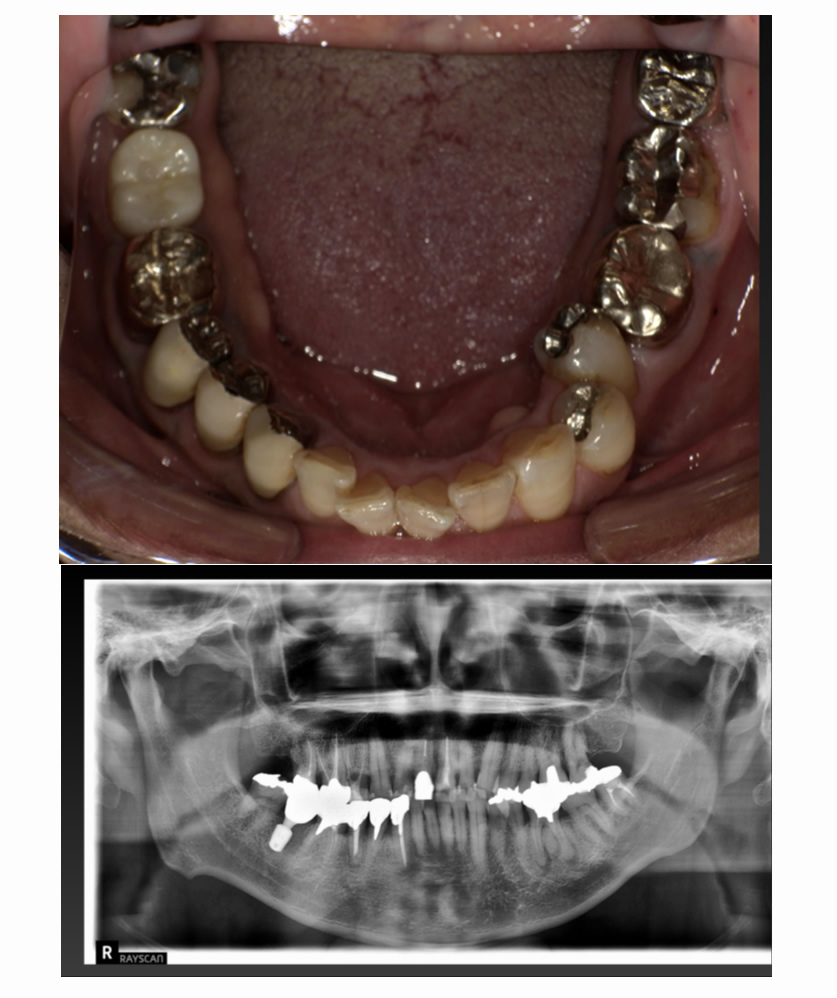

06 症例

歯が割れて痛いのでインプラント希望

Before

After

| 治療内容 | 歯が割れていて咬むと痛いのでインプラント希望 |

| 患者さま | 60代女性 |

| 主訴 | 咬むと痛いのでインプラントにしたい |

| 治療期間(目安) | 3ヶ月 |

| 治療費(税込:目安) | ¥518,100 |

| リスク | 術後に多少の痛みや腫れが出ることがある。歯肉退縮がおきると、歯と歯肉の間に隙間が生じることがあります。 |